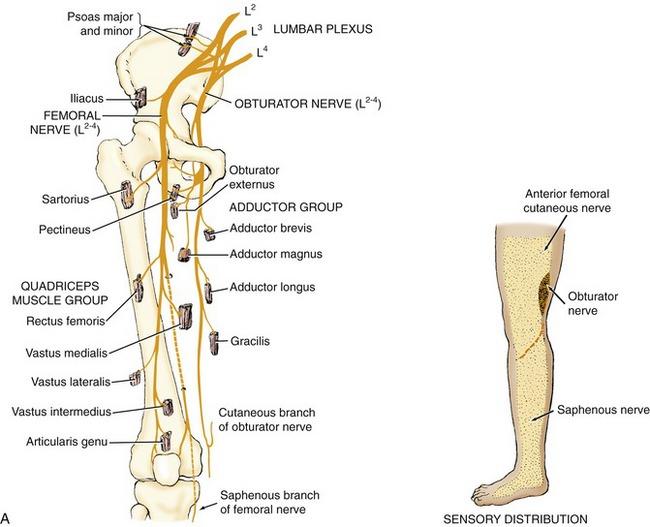

Which two important nerves come from the lumbar plexus?

femoral and obturator

The femoral nerve is formed from ventral rami of spinal cord levels ___________

L2-L4

The obturator nerve is formed from ventral rami of spinal cord levels ___________

L2-L4

What is the path of the femoral nerve?

located superficial to iliacus

runs deep to inguinal ligament to enter anterior thigh

most lateral content of the femoral triangle

Which muscles are innervated by the femoral nerve?

all muscles of anterior thigh: sartorius, rectus femoris, vastus lateralis, vastus medialis, vastus intermedius

the iliacus

and half of pectinius

What is the path of the obturator nerve?

runs medial to psoas major in pelvis

enters medial thigh through obturator foramen

splits into deep and superficial branches at adductor brevis

Which muscles are innervated by the obturator nerve?

anterior and posterior branches?

all medial thigh muscles: gracilis, pectinius, adductor longus, adductor brevis, and adductor magnus (adductor part)

posterior branch is adductor magnus

anterior branch is to all other muscles

origin course and distribution of obturator n

O L2-L4

C descends along medial border of psoas and enters thigh through obturator foramen through with obturator artery and vein. divides into anterior and posterior branches that straddle adductor brevis.

D medial muscles of thigh except hamstring part of adductor magnus

origin and distribution of anterior branch of obturator nerve

O obturator n

D adductor longus, brevis, gracilis and pectineus

origin and distribution of posterior branch of obturator nerve

O obturator n

D obturator externus and adductor magnus (adductor part)

origin and distribution of femoral nerve

O L2-L4

D iliacus, flexors of the hip and extensors of the knee